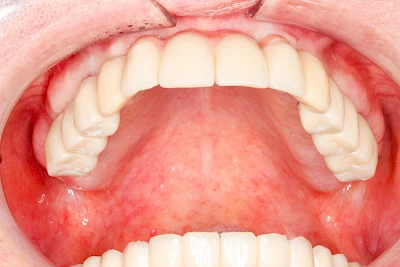

Fehlen einzelne Zähne und die Nachbarzähne sind unbeschadet oder gut zahnärztlich versorgt, werden immer häufiger Implantate gewählt, um die Lücken zu schließen. Auch bei größeren oder verteilten Lücken, wenn keine herausnehmbare Prothese gewünscht ist, werden Implantate für Kronen- bzw. Brückenversorgungen gesetzt. In Einzelfällen entscheiden sich sogar zahnlose Patienten für eine festsitzende Versorgung auf Implantaten.

Varianten zur Verankerung von festsitzendem Zahnersatz auf Implantaten